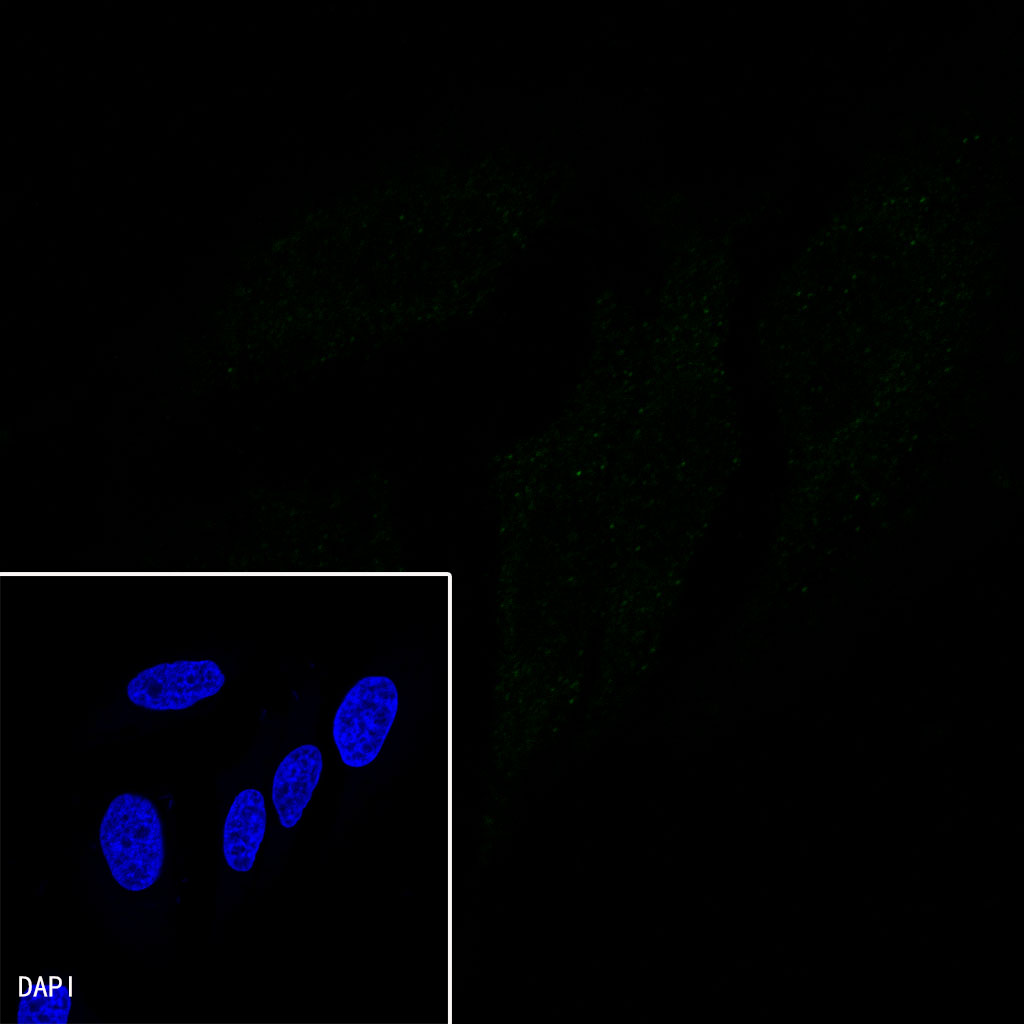

ICC shows positive nuclear staining in SW480 cells. Anti-CDX2 antibody was used at 1/200 dilution and incubated overnight at 4°C. Goat polyclonal Antibody to Rabbit IgG – H&L (Alexa Fluor® 488) was used as secondary antibody at 1/1000 dilution.The cells were fixed with 4% PFA and permeabilized with 0.1% PBS-Triton X-100. Nuclei were countersained with DAPI.

ICC shows positive nuclear staining in HCT-116 cells (Low expression). Anti-CDX2 antibody was used at 1/200 dilution and incubated overnight at 4°C. Goat polyclonal Antibody to Rabbit IgG – H&L (Alexa Fluor® 488) was used as secondary antibody at 1/1000 dilution.The cells were fixed with 4% PFA and permeabilized with 0.1% PBS-Triton X-100. Nuclei were countersained with DAPI.

Negative control: ICC shows negative staining in HeLa cells. Anti-CDX2 antibody was used at 1/200 dilution and incubated overnight at 4°C. Goat polyclonal Antibody to Rabbit IgG – H&L (Alexa Fluor® 488) was used as secondary antibody at 1/1000 dilution.The cells were fixed with 4% PFA and permeabilized with 0.1% PBS-Triton X-100. Nuclei were countersained with DAPI.